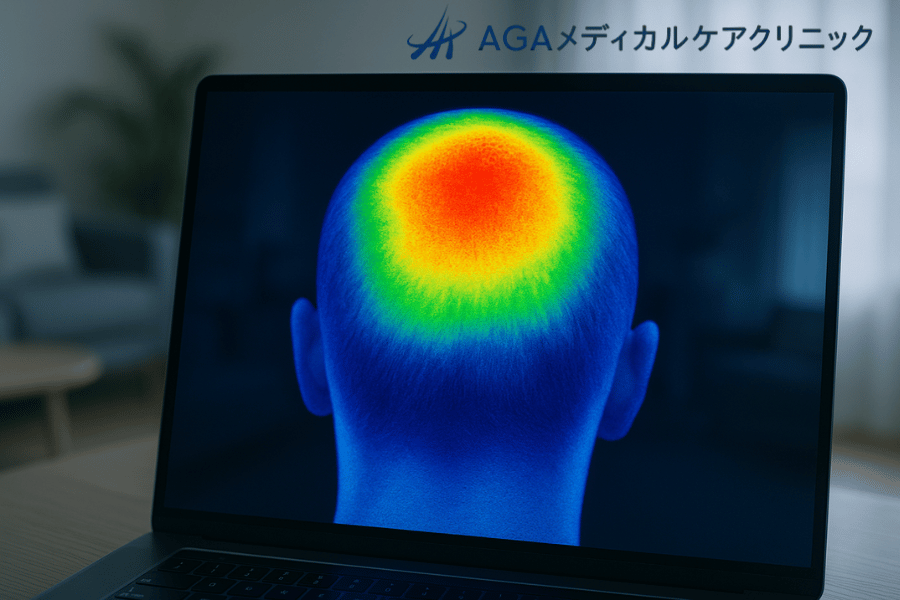

体の表面温度を色で表示するこの技術によって、今まで目には見えなかった頭皮の血流の問題点が明らかになります。

サーモグラフィーのカメラは、この目に見えない赤外線を特殊なセンサーで捉え、温度の高い部分を赤や黄色、低い部分を青や緑といったように、色の違いで視覚的に表現します。

血液は熱を運ぶ役割を担っているため、血流が豊富な部分は温度が高く、滞っている部分は温度が低く映し出されます。

この原理を利用して、頭皮全体の血行のバランスや、特に血行が悪い箇所を特定するのです。

サーモグラフィー検査の最大の特長は、頭皮全体の血行状態を一枚の画像で直感的に把握できる点にあります。

色分けされた温度分布図は、専門家でなくても血行の良い部分と悪い部分を一目で理解するのに役立ちます。

この画像から、薄毛のリスクや頭皮の健康状態に関する多くの情報を読み解くことができます。

撮影されたサーモグラフィー画像は、頭皮の血行状態をいくつかのパターンに分類して評価します。例えば、頭部全体が均一に暖かい色(赤や黄色)で表示されていれば、血行は良好と判断できます。

一方、頭頂部や生え際など、特定の部位が周囲に比べて著しく低温(青や緑)になっている場合、その部分の血行が特に滞っていることを示します。

健康で血行が良好な頭皮は、サーモグラフィーで見ると、中心部から外側に向かってなだらかに温度が分布し、全体的に均一な暖かい色を示します。